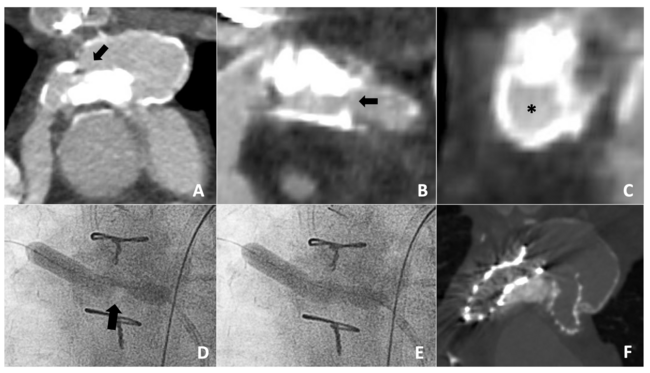

A 25-year-old man with a history of D-transposition of the great arteries who underwent staged palliation culminating in an arterial switch procedure with a LeCompte maneuver by 1 month of age, followed by 2 subsequent surgical aortic valve replacements (AVR). During the second AVR, he required branch pulmonary artery (PA) reconstruction with homograft material as a result of longstanding bilateral branch PA stenoses. In the setting of progressive bilateral branch PA stenoses, he was brought forward for branch PA stenting. A pre-procedural cardiac computed tomographic angiogram (CTA) revealed severe bilateral ostial PA stenoses measuring 4 x 5 mm and 8 x 15 mm within the right and left PAs with distal reference diameters of 11 x 13 mm and 21 x 25 mm, respectively. Heavy circumferential right PA calcification was present, presumed to be homograft tissue from the prior repair (Figure 1A-C).

The procedure was carried out with bilateral venous access and simultaneous wiring of the branch PAs. Initial angioplasty of the right PA origin with an 8-mm Charger balloon (Boston Scientific) inflated to 10 atm without alleviation of a mid-balloon waist. Attempts to place a covered stent prior to a more aggressive angioplasty were unsuccessful because of an inability to deliver a long 12-French sheath across the heavily calcified lesion. As such, the decision was made to perform IVL to the ostial right PA. A 0.014-inch exchange length guide wire was advanced into the distal right PA and a 7-mm Shockwave IVL balloon was advanced over the wire and into the right PA. The balloon was inflated to 4 atm and a total of 60 lithotripsy pulses were delivered, resulting in near complete relief of the mid-balloon waist, suggesting adequate lithotripsy (Figure 1D and E). Following IVL, 2 covered Cheatham-Platinum stents (CCPS) (Numed Inc.) and a Palmaz 4010 XL stent (Cordis) were implanted and post-dilated with a 12-mm balloon to 30 atm, resulting in a substantial improvement in the right PA caliber to a minimum diameter of 10 mm. Left PA stenting was performed without difficulty, resulting in substantial reduction in the right ventricular systolic pressures and a decrease in the right PA gradient from 55 to 15 mm Hg. There were no periprocedural complications and the patient was discharged within 24 hours. A CTA performed several months later demonstrated widely patent branch PA stents (Figure 1F).